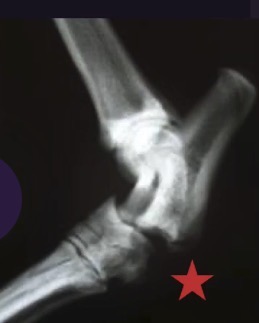

What view is this? When stress is applied, what joint is opened up? Is this unstable or stable?

lateral view of tarsus

Stress applied to open up plantar aspect of tarsus, identifying that the proximal intertarsal joint is unstable